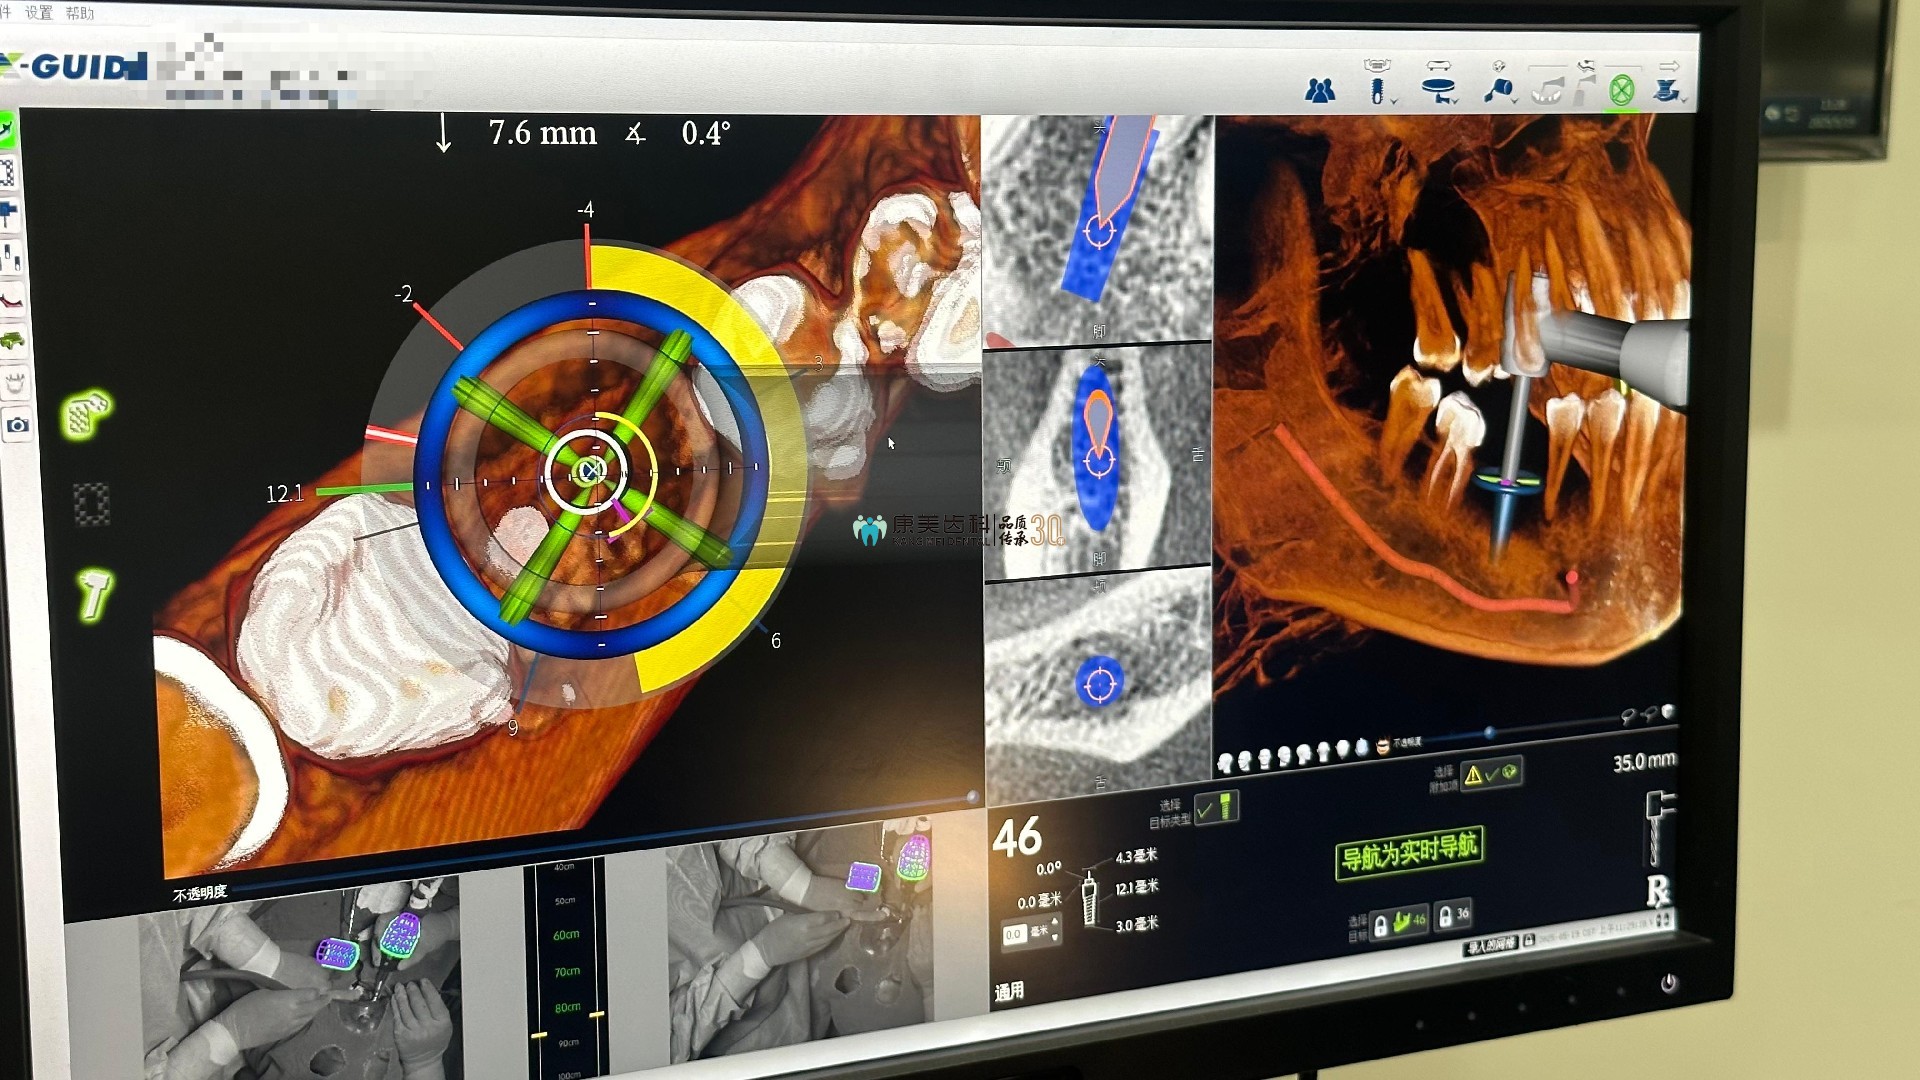

此次手術通過Nobel X-Guide三維實時導航系統,結合計算機輔助設計(CAD)與動态追蹤技(jì )術,以0.1毫米級誤差精(jīng)度,為(wèi)複雜骨條件患者實現“微創、高效、穩定”的缺牙修複新(xīn)方案。

三維動态導航:實時呈現颌骨内神經、血管的立體(tǐ)影像,術中(zhōng)全程“透視”避讓關鍵解剖結構,安(ān)全性提升300%;

數字化建模:術前掃描患者颌骨CBCT數據,在DTX STUDIO軟件中(zhōng)重建三維虛拟模型,規劃種植體(tǐ)植入路徑;

動态追蹤配準:通過X-Mark技(jì )術匹配患者口内實際解剖結構與虛拟模型;

導航精(jīng)準植入:術中(zhōng)實時調整鑽針角度與深度,種植體(tǐ)與鄰牙、神經管保持1.2毫米安(ān)全距離,完美避開風險區(qū)。